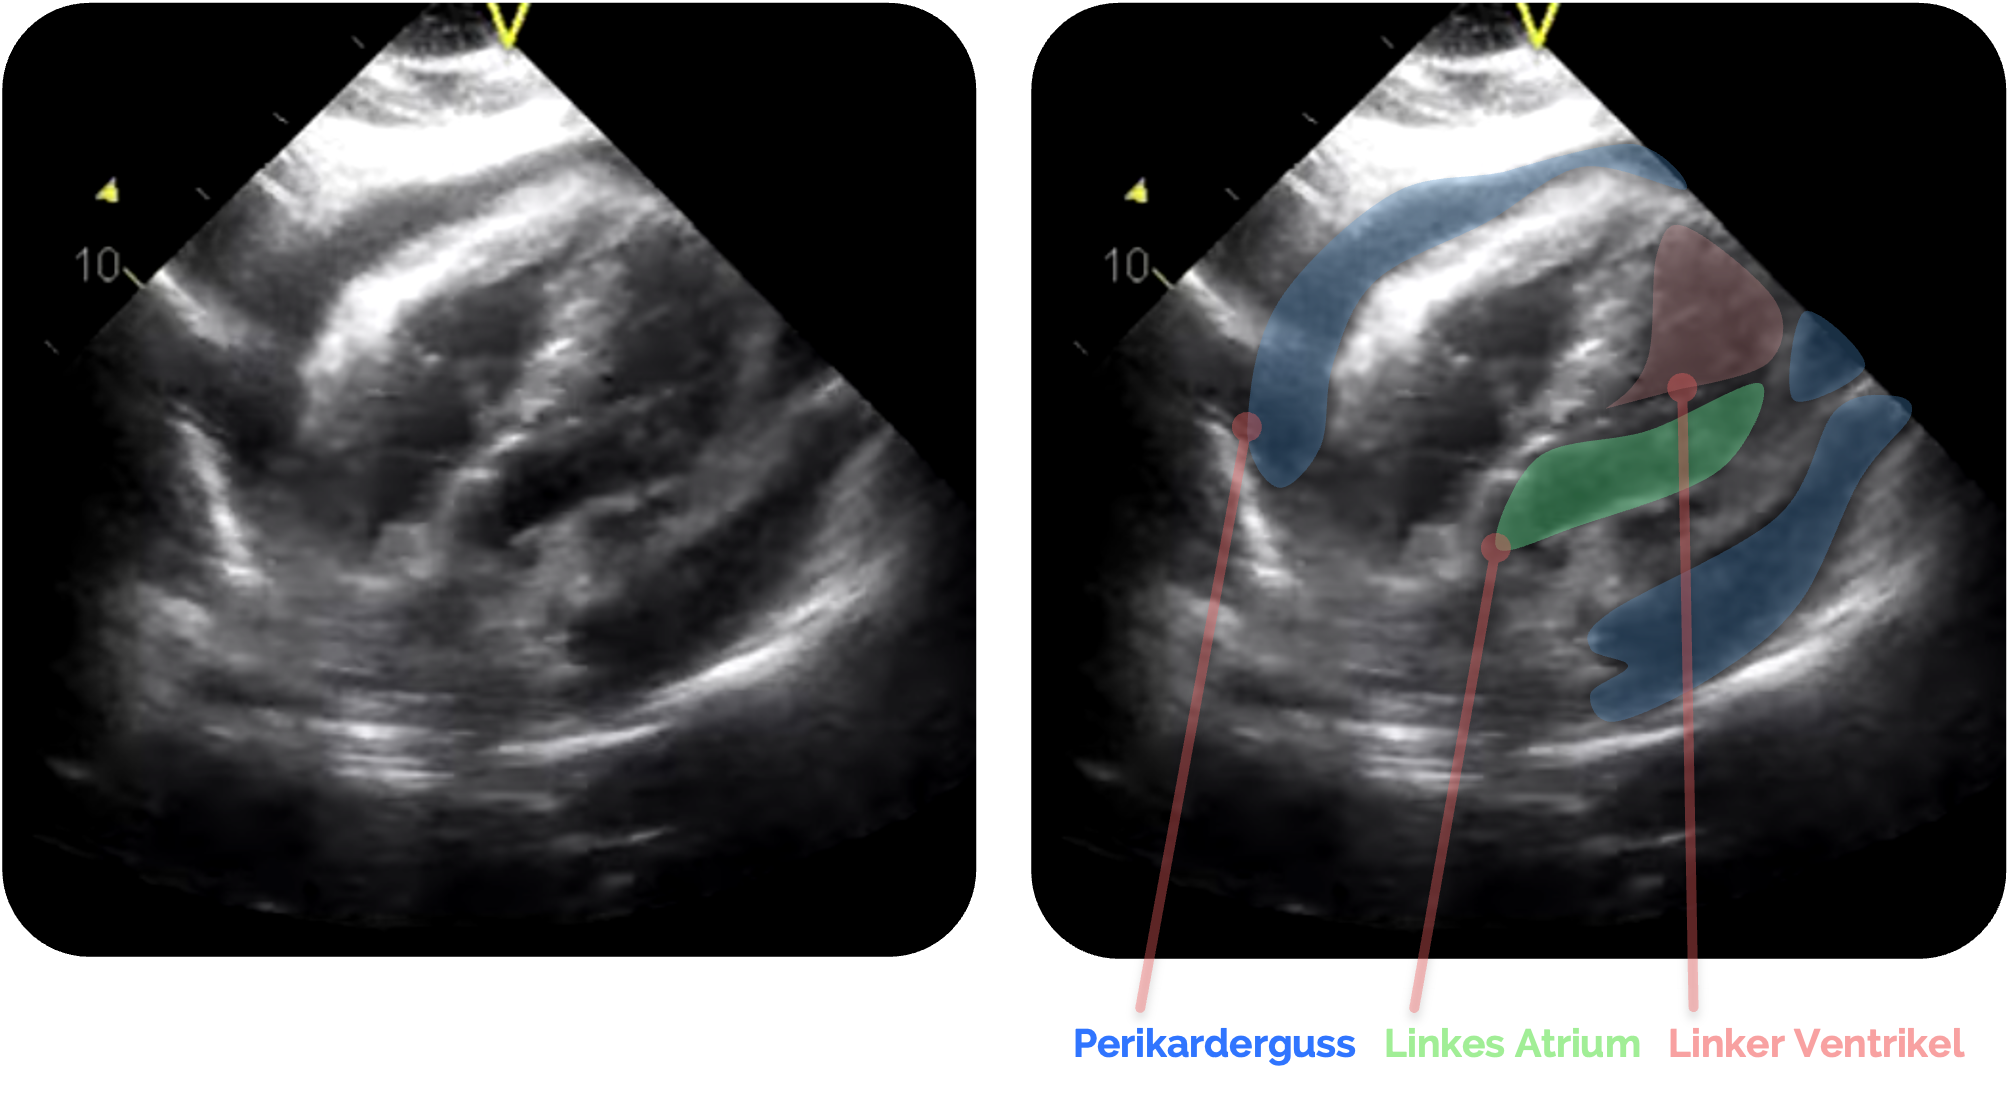

Figure 1 aus Jakobsen, L.K., Bøtker, M.T., Lawrence, L.P. et al. Systematic training in focused cardiopulmonary ultrasound affects decision-making in the prehospital setting – two case reports. Scand J Trauma Resusc Emerg Med 22, 29 (2014). https://doi.org/10.1186/1757-7241-22-29. Das Bild wurde zugeschnitten und es wurden Markierungen hinzugefügt.

Zunächst sichere Orientierung

- Leber

im Vordergrund (Liver ➜) - Dahinter Zwerchfell

(ZF ➜) - Direkt darüber das Herz, meist beginnend mit dem rechten Atrium (RA ➜) und rechten Ventrikel (RV ➜) und folgend mit dem linken Atrium

(LA ➜) und linken Ventrikel (LV ➜) - Perikard

als echoreiche Linie, die das Herz umgibt (PK➜)

Figure 1 aus Jakobsen, L.K., Bøtker, M.T., Lawrence, L.P. et al. Systematic training in focused cardiopulmonary ultrasound affects decision-making in the prehospital setting – two case reports. Scand J Trauma Resusc Emerg Med 22, 29 (2014). https://doi.org/10.1186/1757-7241-22-29. Das Bild wurde zugeschnitten und es wurden Markierungen sowie Beschriftungen hinzugefügt.

Perikarderguss

Sonographisch zeigt sich ein Perikarderguss als echoarmer (dunkler) Spalt zwischen dem Myokard und der echoreichen (hellen) Begrenzung des Perikards

In der subxiphoidalen Projektion liegt der Erguss zunächst meist posterior des Herzens und breitet sich mit zunehmender Flüssigkeitsmenge zirkulär

Das Perikard